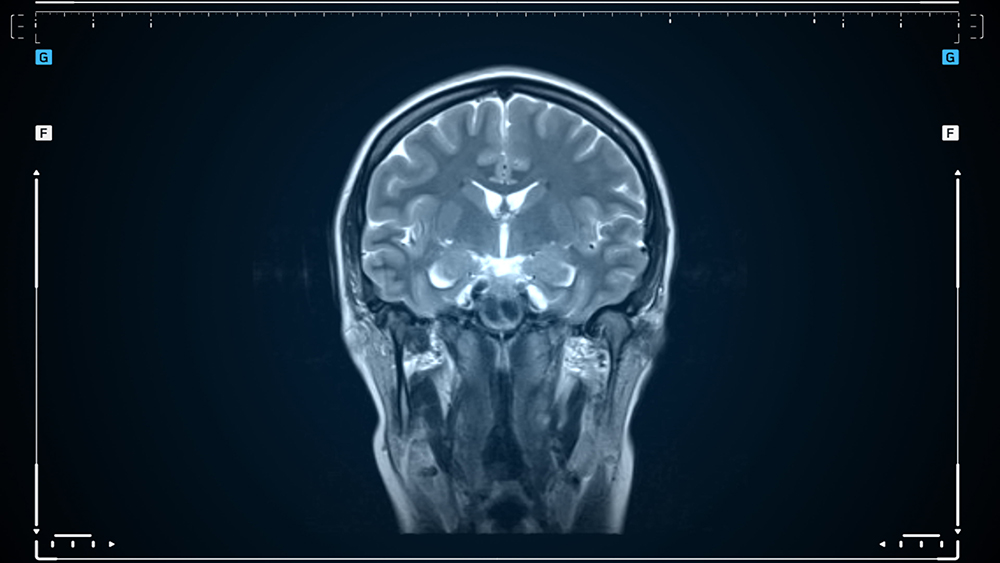

- MRI 및 MRA: 뇌혈관의 구조와 혈류를 확인하기 위한 주요 영상 진단 방법입니다.

- 뇌혈관 조영술: 모야모야병의 확진을 위해 가장 효과적인 검사로, 뇌혈관의 비정상적인 모양을 정확히 확인할 수 있습니다.